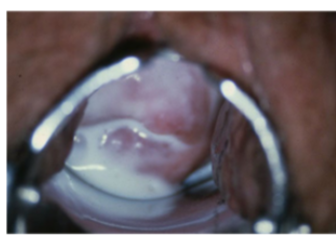

Candida-infectie